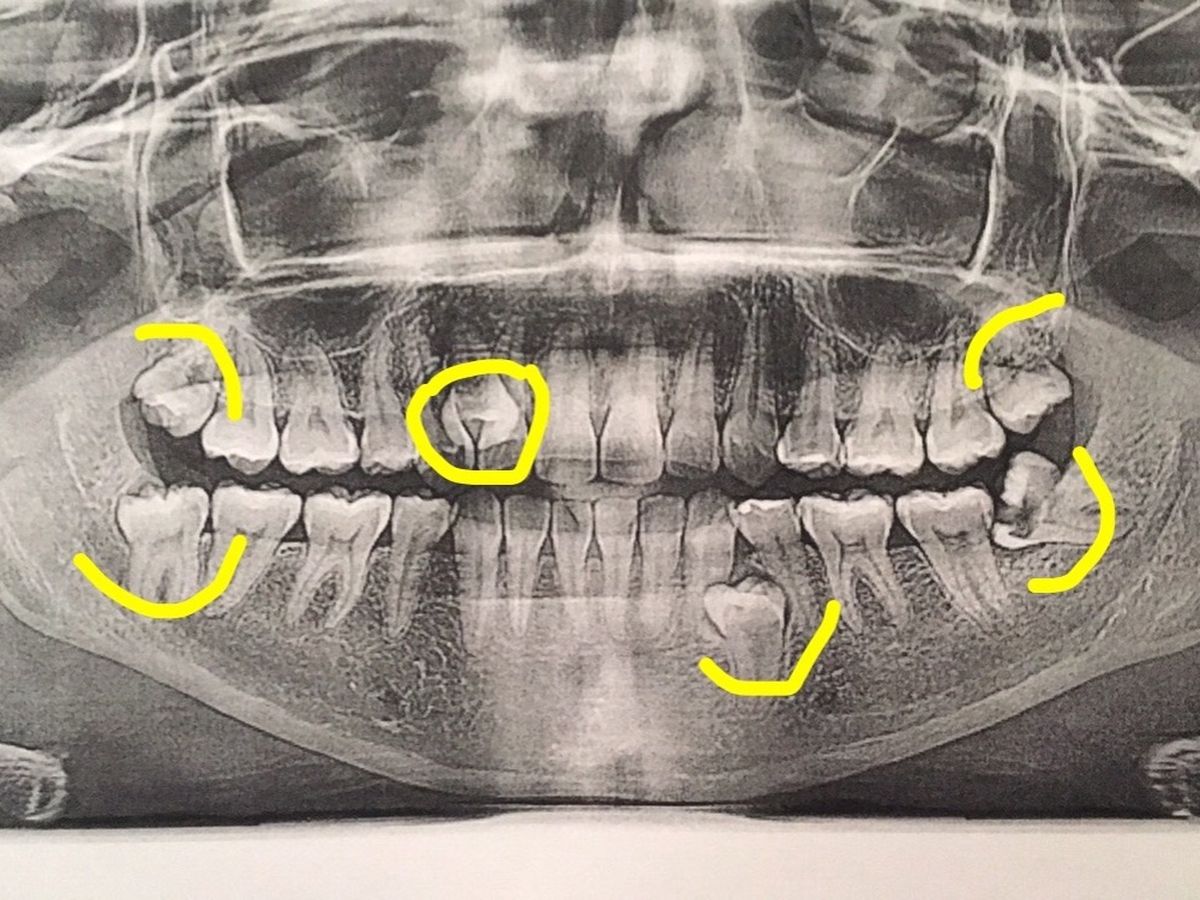

I have 4 wisdom teeth coming, one of them coming in completely sideways that now has a hole in it, and is close to hitting my jaw bone that needs to be out urgently. It has been causing pain, fogginess, and migraines.

In addition to that, I have 2 extra (supenumerary) teeth, one that is already out, and the other on the same side as the impacted wisdom tooth, creating pain and discomfort as well.